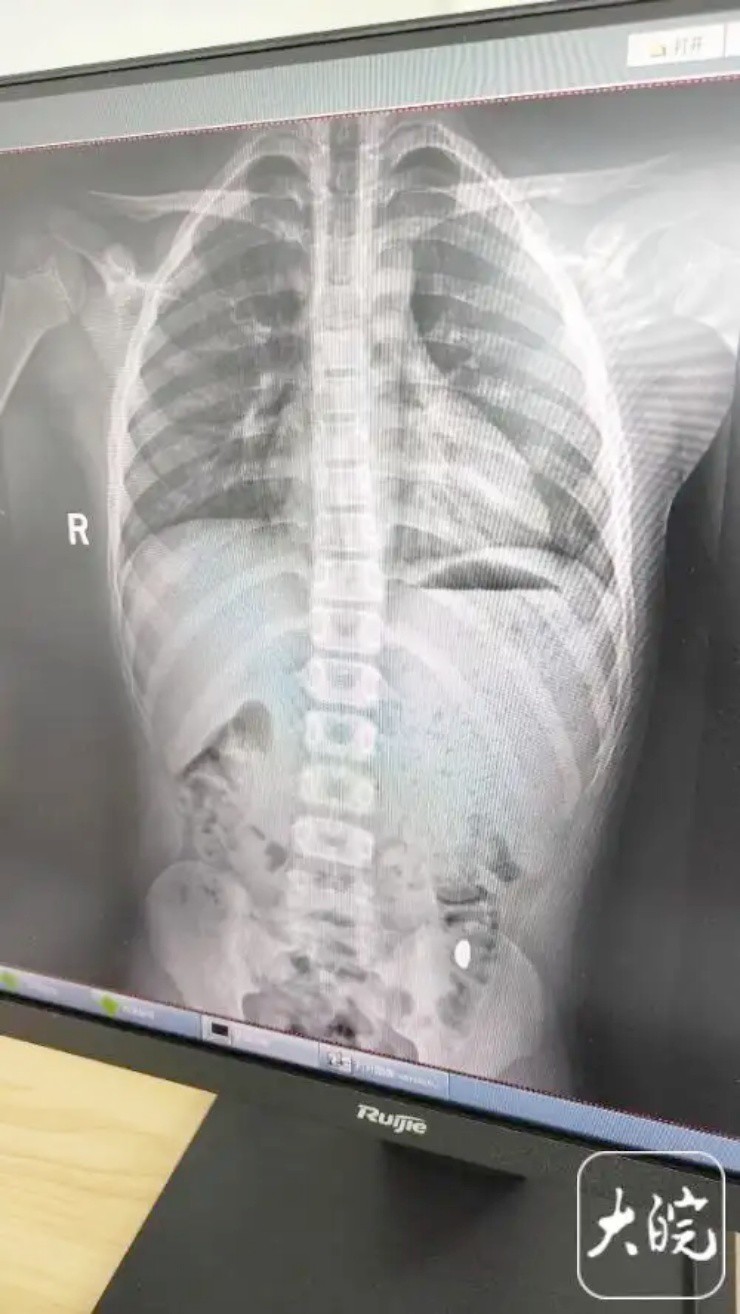

Trong bệnh án tại đây ghi rằng, trẻ đã vô tình nuốt phải khoảng 10 gram vàng cách đây 5 ngày. Trong thời gian này, cô Ji đã tìm hai lần nhưng k không thấy vàng trong chất thải của trẻ. Trẻ cũng không có triệu chứng nào như đau bụng hay nôn mửa. Kết quả chẩn đoán cho thấy có dị vật trong dạ dày.